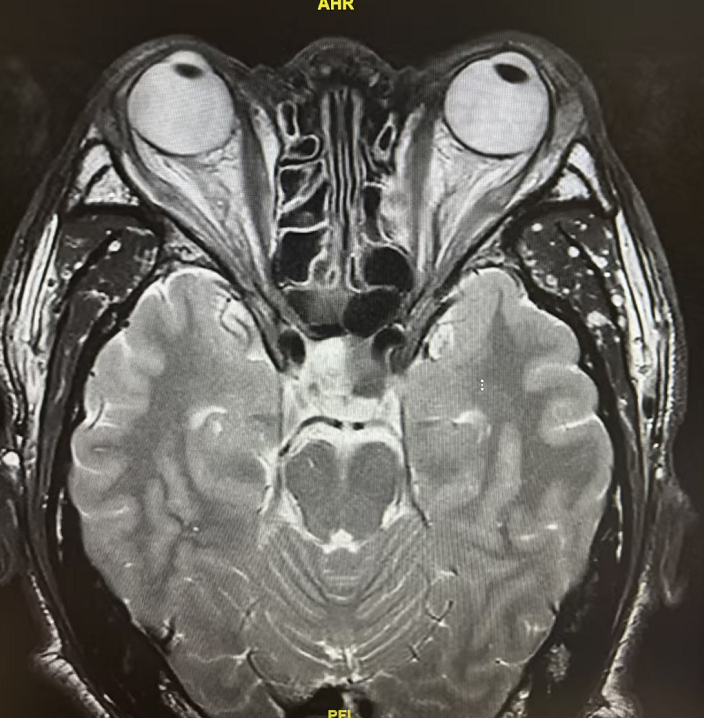

患者为21岁年轻女性,因“月经紊乱6月余”来院就诊。当地医院MRI提示垂体占位,激素检验显示泌乳素高达273ng/ml(较正常值高了11倍)。经我院神经外科进一步评估,确诊为垂体瘤。

术前眼科会诊发现,患者虽自觉视力无明显下降,但视野检查已提示右眼生理盲点扩大、周边颞上方片状视野缺损——这是垂体瘤向上压迫视交叉的早期信号。内分泌科同步介入,全面评估激素水平,为手术保驾护航。术后泌乳素即刻恢复正常,术后6天康复出院。

患者52岁男性,因摔倒致头部外伤急诊入院,行颅脑CT检查意外发现:鞍区占位性病变。入院后进一步检查显示,患者泌乳素升高,性腺、甲状腺、肾上腺皮质功能均减退,考虑为垂体瘤压迫正常垂体组织有关,手术指征明确。